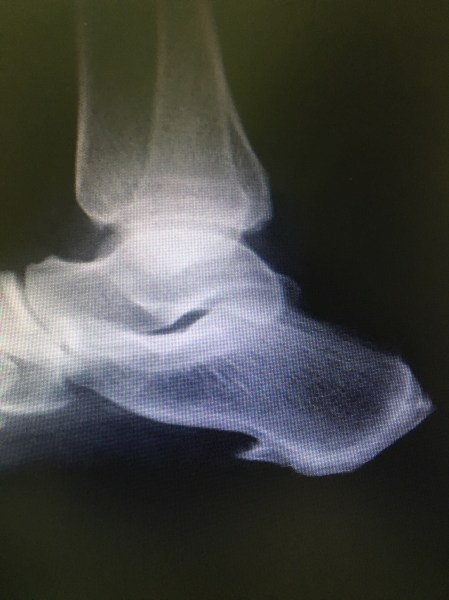

X-Ray may reveal a calcaneal bony spur. The spur is asymptomatic mostly, the inflammation around it causes pain.

Ultrasound is diagnostic and it shows the quantum of inflammation and the extent of area involved.